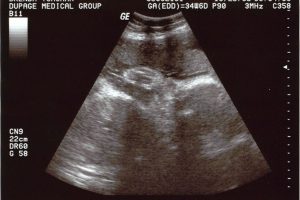

35 Week Ultrasound Today

This morning we had our 35 week ultrasound, and all checked out perfectly. The baby is now 5 lbs 12 ounces, head is down and all of the body measurements were normal. The baby is also moving a lot more as time goes on. Brenda said a lot more then with the twins (probably because […]